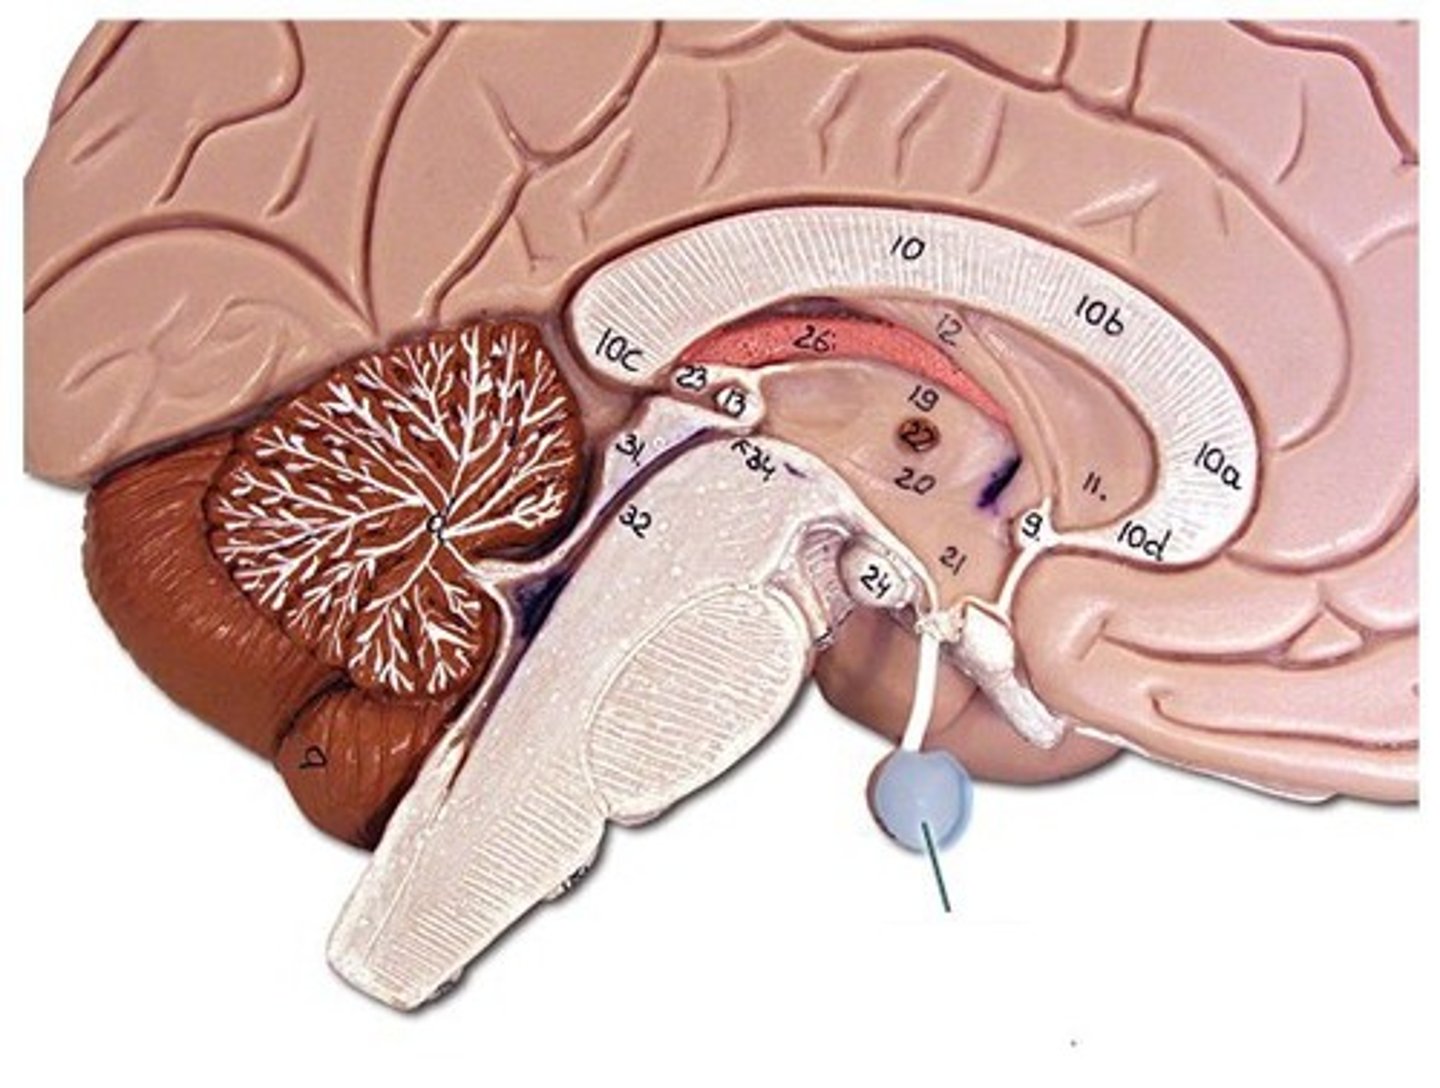

hypothalamus

knowt flashcard image

pituitary gland (hypophysis)

adenohypophysis: anterior pituitary gland

neurohypophysis: posterior of pituitary gland

red squared

pineal gland